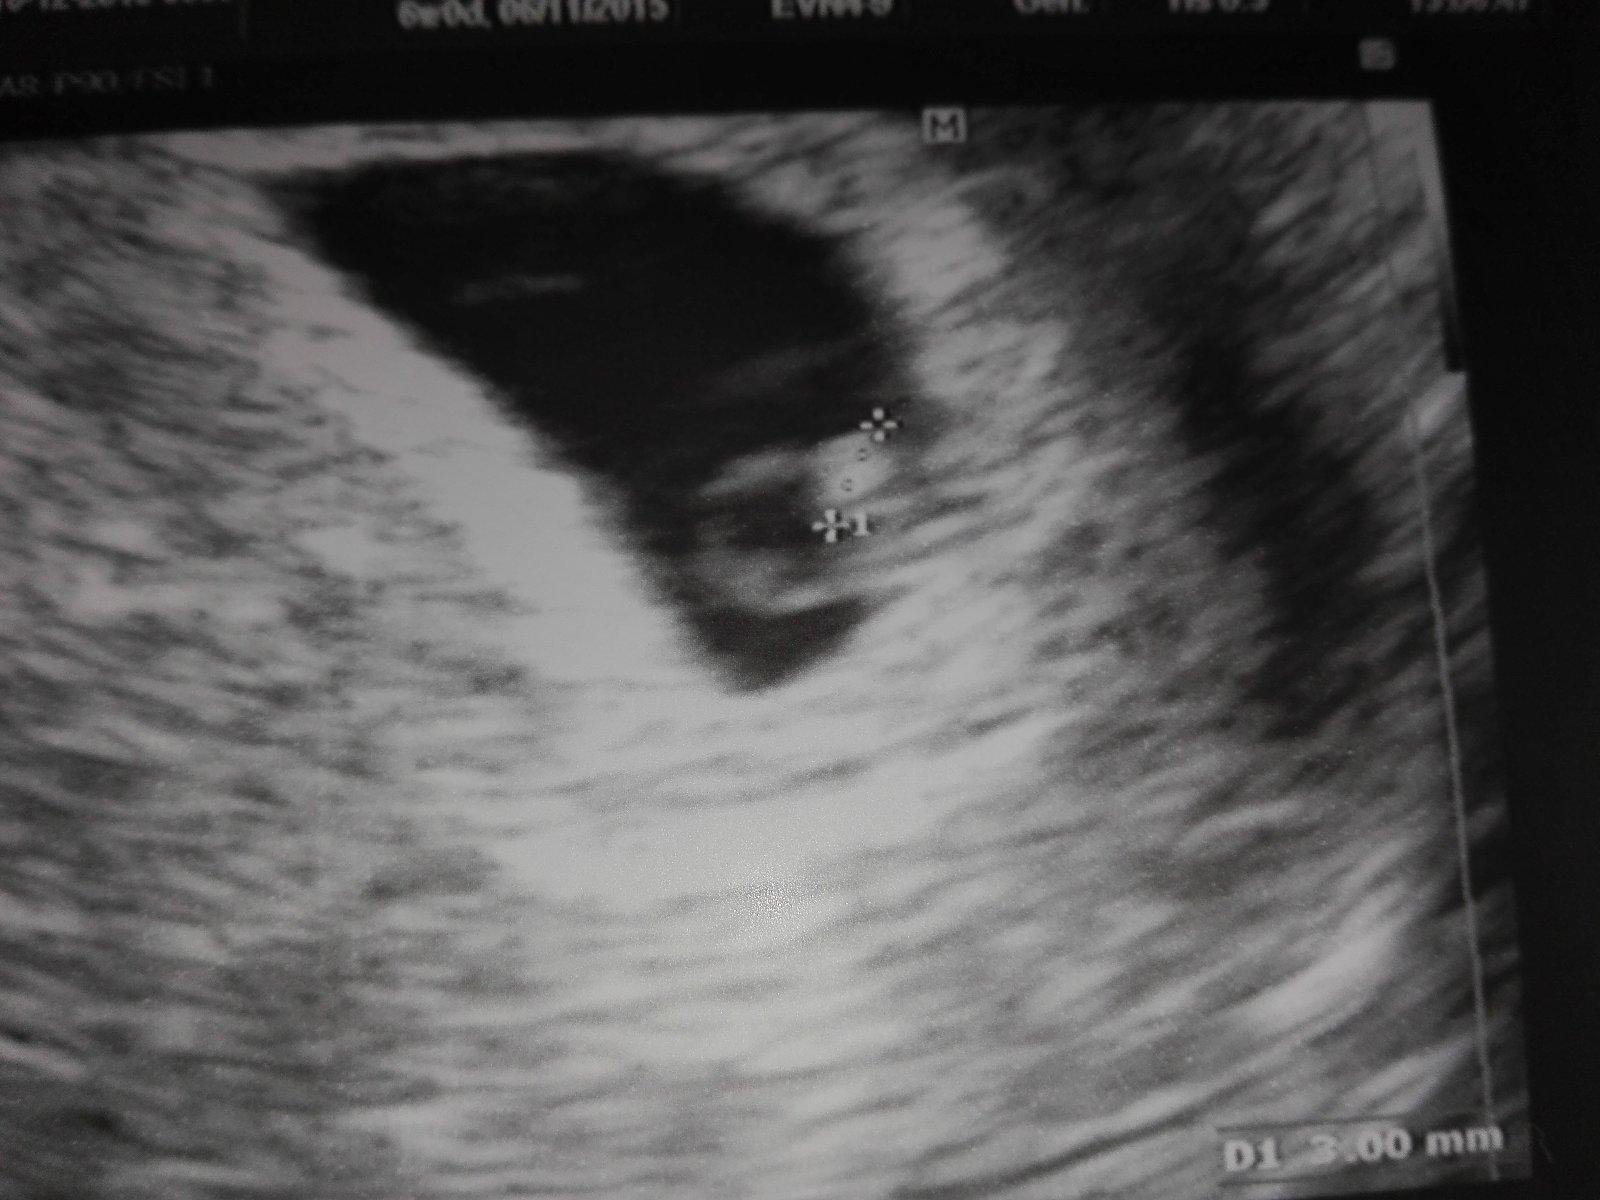

SRDIEČKO ♥ nádherne bilo! ♥♥♥ to ako blikotkalo na obrazovke bolo to najkrajšie čo som doposial videla!!!!!! ♥♥♥ máme 3mm a som neskutočne šťastná !!!!! ♥♥♥ kontrola presne o mesiac 🙂 tešííííííííímsaaaaaaa.len musim ist do roboty, tak ajojte :/